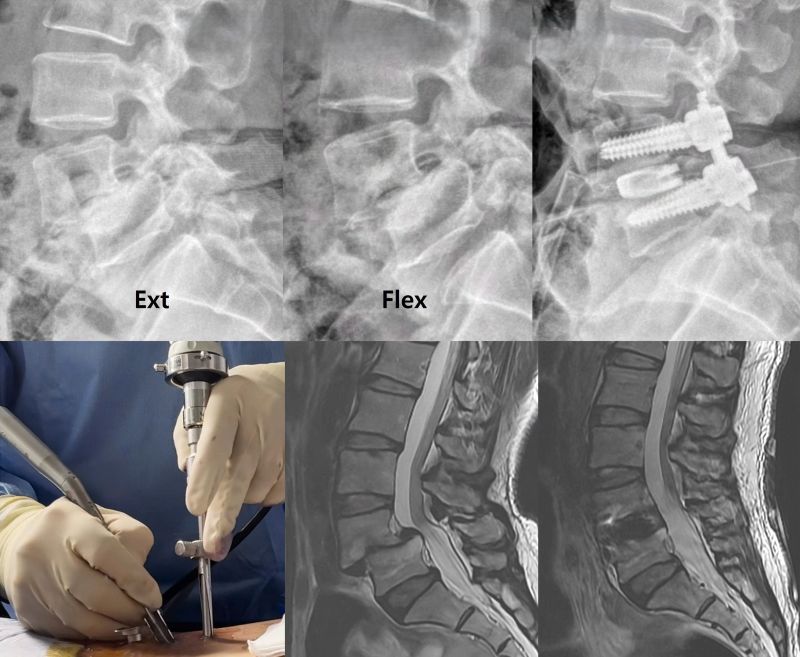

- X-rays of the Spine: Standing lateral, anteroposterior (AP), and oblique views are standard. Lateral X-rays are crucial for identifying and grading the spondylolisthesis (Meyerding classification). **Functional X-rays (flexion and extension views)** are particularly important for diagnosing instability, as they can demonstrate abnormal movement or an increase in slippage between vertebrae during motion. This is especially relevant when examining the lumbar or cervical spine.

- Interbody Fusion: Bone graft or an interbody cage (a device filled with bone graft material) is placed into the disc space after removal of the intervertebral disc. This can be done via posterior approaches (PLIF - Posterior Lumbar Interbody Fusion; TLIF - Transforaminal Lumbar Interbody Fusion), an anterior approach (ALIF - Anterior Lumbar Interbody Fusion), or lateral approaches (LLIF/XLIF). The figure showing interbody fusion by placing a second cage via a minimally invasive neurosurgical transforaminal approach illustrates one such technique.

- Instrumentation (Internal Fixation): Pedicle screws, rods, plates, or interbody cages are often used in conjunction with fusion to provide immediate stability, hold the vertebrae in the desired position, and enhance fusion rates. Surgical treatment of instability of the cervical spine by anterior fusion might involve fixing the bodies of the cervical vertebrae with a plate and screws after discectomy and graft placement.

The figure depicts an operation for interbody fusion, specifically by placing a second interbody cage to stabilize lumbar vertebrae affected by instability. A minimally invasive neurosurgical transforaminal approach is being utilized on the left side, subsequent to prior pedicle screw placement on the right.